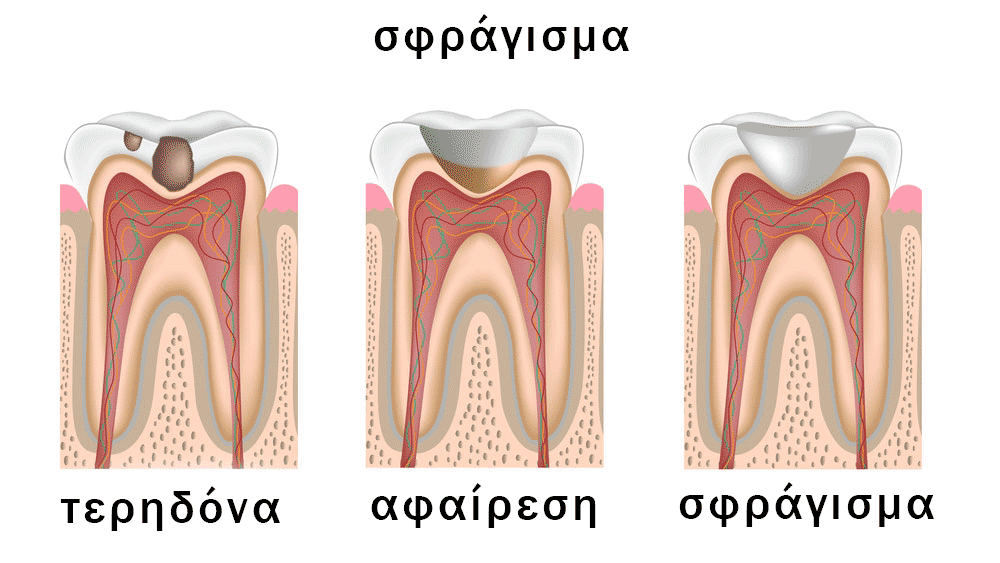

Αισθητικά Σφραγίσματα

Τα αισθητικά σφραγίσματα ή αλλιώς άσπρα σφραγίσματα, επίσης γνωστά ως «ρητίνη», είναι μια σύγχρονη μέθοδος με την οποία μπορούμε να αποκαταστήσουμε τερηδονισμένα δόντια ή να αντικαταστήσουμε παλιά μεταλλικά σφραγίσματα, με απόλυτα φυσικό τρόπο και αισθητικό αποτέλεσμα.